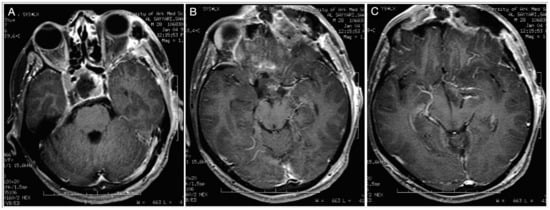

3.3.2. Case #5: Extension beyond the Lateral Wall of the Cavernous Sinus

3.3.3. Case #6: Encasement of the Posterior Communicating and Anterior Choroidal Artery